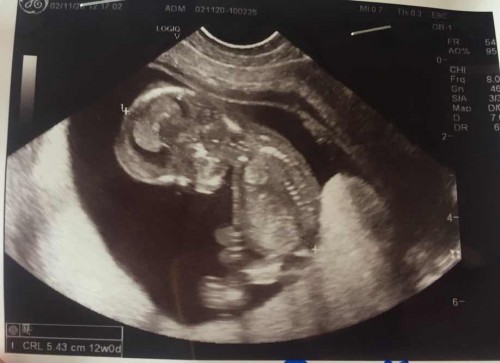

เจ้าตัวน้อยของแม่

แค่ได้เห็นลูก แม่ก็มีความสุขมากแล้ว

ภาพอัลตราซาวด์ชัดมากเลยค่ะ อันนี้กี่วีคค่ะ